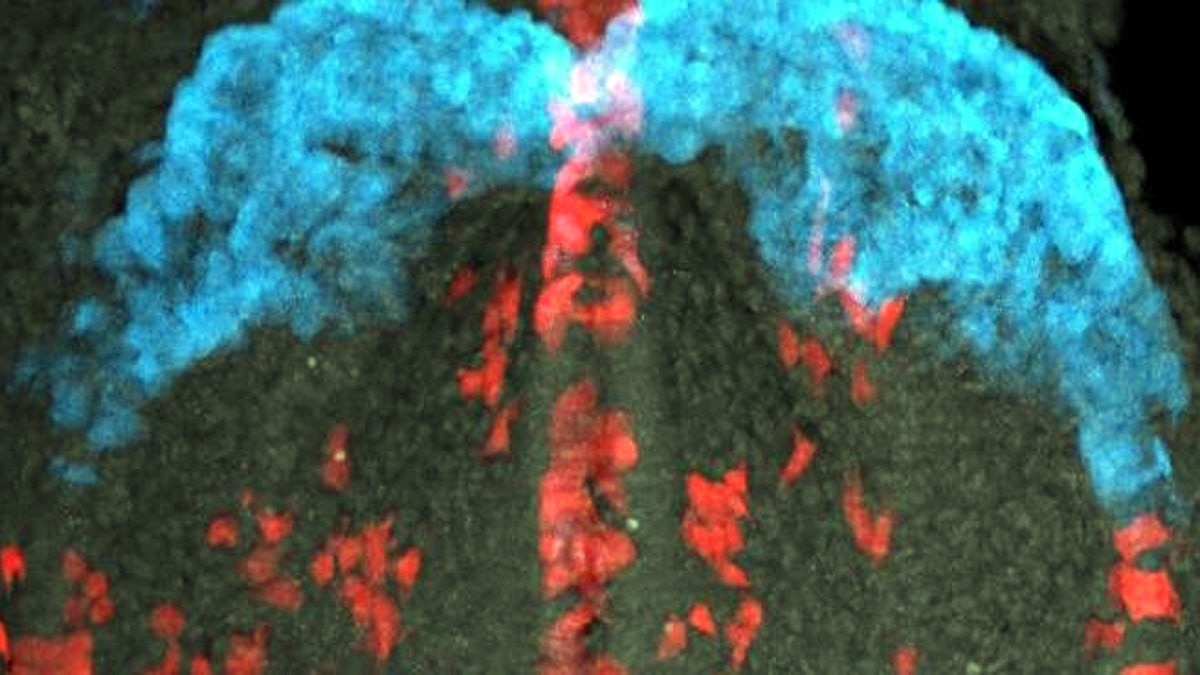

क्या आपने सोचा है कि बच्चा बनने की पहले पल में क्या होता है? वैज्ञानिकों ने पाया है कि जब शुक्राणु अंडे को छूता है, तो अंडे से जिंक नाम की चीज निकलती है. यह जिंक इतनी तेजी से बाहर आती है कि एक चमकदार रोशनी बन जाती है. यह फ्लैश पटाखों के फूटने जैसा लगता है. यह चमक सिर्फ सुंदर नहीं, बल्कि बताती है कि अंडा कितना अच्छा है. अच्छे अंडे से स्वस्थ बच्चा बनेगा.

अंडे के अंदर बहुत जिंक जमा रहता है. शुक्राणु के एंजाइम अंडे को जगाते हैं. इससे अंडे में कैल्शियम बढ़ जाता है. कैल्शियम बढ़ने पर अंडे की सतह पर छोटी थैली फट जाती हैं. इनसे जिंक बाहर आता है – 10 अरब जिंक कण 4-5 लहरों में. यह सब 2-3 सेकंड में हो जाता है.

वैज्ञानिकों ने स्पेशल रसायनों से इसे देखा. एक रसायन कैल्शियम को हरा रंग देता है, दूसरा जिंक को. माइक्रोस्कोप से फ्लैश साफ दिखा. पेपर में लिखा है कि जिंक कैल्शियम के साथ सेकेंडों में निकलता है.

अध्ययन में 12 अच्छे अंडे और 7 कम अच्छे अंडे देखे गए. अच्छे अंडे में जिंक की चमक ज्यादा तेज थी. कम अच्छे में कम. वैज्ञानिकों ने गणना की – अच्छे अंडे की चमक ज्यादा (p

जिंक फ्लैश की ताकत से पता चलता है कि अंडा अच्छा है या नहीं. मजबूत फ्लैश मतलब अच्छा भ्रूण बनेगा. यह IVF (टेस्ट ट्यूब बेबी) में बहुत काम आएगा. डॉक्टर अच्छे अंडे आसानी से चुन सकेंगे. पेपर कहता है कि यह फ्लैश भ्रूण के विकास का संकेत है. इससे एक ही भ्रूण डालने से जोखिम कम होगा.